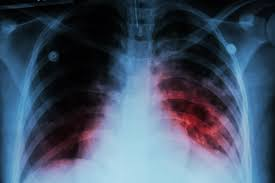

TB

NAN reports that MDR-TB is largely caused by incomplete or improper treatment of TB, including skipped doses, wrong drug combinations, poor-quality medicines, or interruptions in drug supply.

It can also occur when individuals are directly infected with already-resistant strains, particularly in areas with weak health systems and delayed diagnosis.